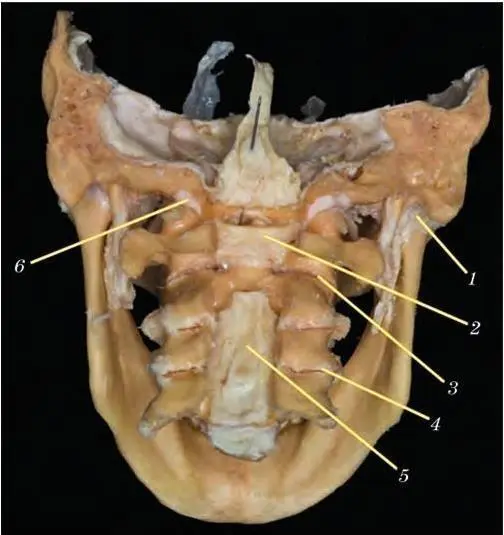

Рис. 45. Височно-нижнечелюстной сустав.Соединения шейных позвонков. Натуральный анатомический препарат. Полимерное бальзамирование. Дуги позвонков частично удалены. Вид сзади:

1 – капсула височно-нижнечелюстного сустава; 2 – поперечная связка атланта; 3 – атланто-осевой сустав; 4 – межпозвоночный сустав; 5 – задняя продольная связка; 6 – атланто-затылочный сустав